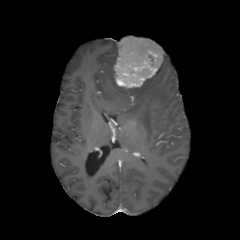

| non-CE T1w (Input) | Residual U-Net (PM) | RF Baseline | PMRF (ours) | CE T1w (GT) |

We qualitatively evaluate the top-performing Residual U-Net (Posterior Mean), RF baseline, and PMRF models (with a patch-overlap of 32 for all and integration steps for the RF baseline as well as the PMRF model) on the held-out test set. For a set of representative cases, Figure 3 compares the non-CE T1w input, Res. U-Net (equivalent to PM), RF baseline, our two-stage PMRF, and the ground truth CE T1w image. Example 1 depicts a metastases patient, example 2 a high-grade glioma patient, and example 3 a meningioma patient. Across these test cases, the Res. U-Net output accurately localizes lesions and captures their overall enhancement intensity but appears overly smooth, and muted in rim heterogeneity and fine texture. The Stage 2 PMRF refinement consistently sharpens lesion boundaries, reinstates subtle vascular and margin details, and restores characteristic enhancement patterns, yielding synthetic images nearly indistinguishable from true post-contrast scans. However, Stage 2 can only refine what the posterior-mean predictor already suggests. If a subtle rim, micro-metastasis, or vessel enhancement is entirely suppressed in Stage 1, Stage 2 has no signal to resurrect it; its perturbations stay within a narrow neighborhood of the Stage 1 output. In contrast, the RF baseline directly predicts the CE signal from the perturbed non-CE image. However, this comes with the limitation of not predicting the CE strength faithful or missing subtle details as in examples 2 and 3.